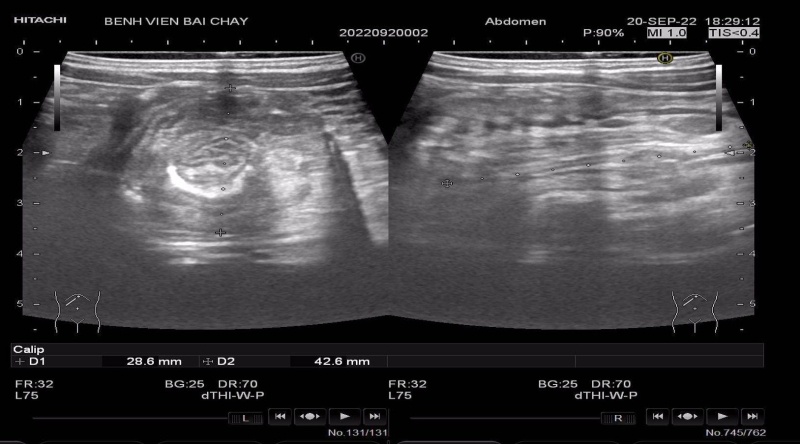

Khi vào viện, trẻ được các bác sĩ thăm khám thấy bụng chướng, nắn đau, sờ có khối lồng ruột vùng hạ sườn phải cứng chắc, di động. Kết quả siêu âm vùng hạ sườn phải có hình ảnh khối hỗn hợp âm kích thước 28x42 mm, gồm nhiều vòng tròn đồng tâm trên lát cắt ngang, bên trong có vài hạch mạc treo.

Hình ảnh trẻ bị lồng ruột qua siêu âm. Ảnh: BVCC.